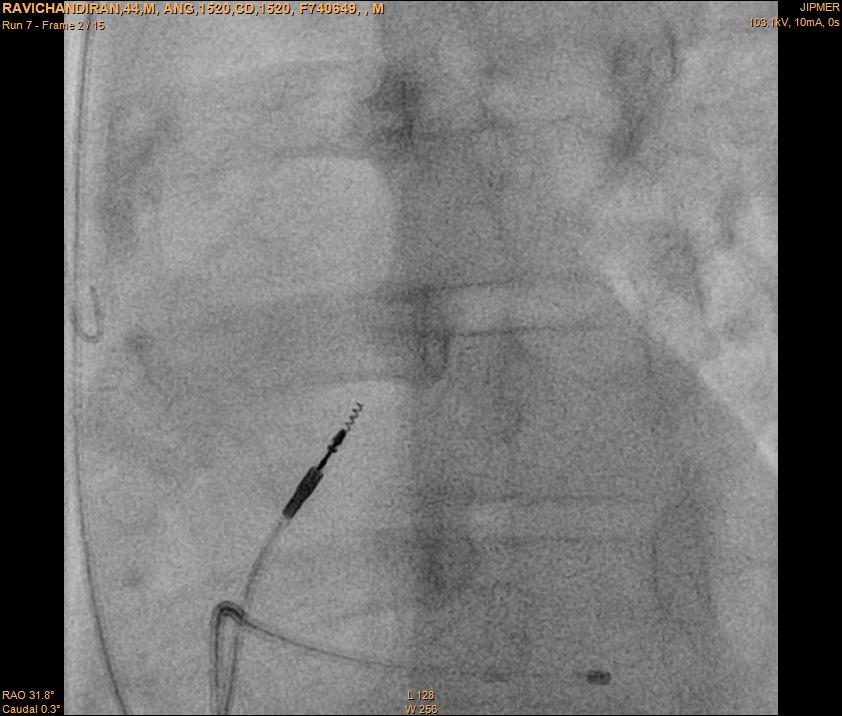

RVOT pacing

• Active fixation lead

• Stylet shaping

rvot_before_screw.jpg

screw.jpg

screwe.jpg

rvot_lead.jpg